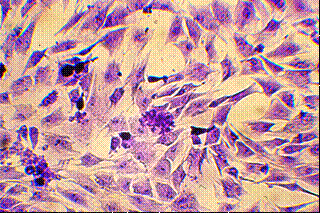

получали монослойную культуру (рис.9)

Рис.5. Монослойная культура клеток нормальных фибробластов